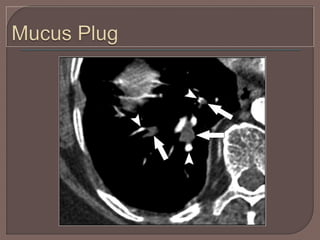

A mucus plug within a bronchus, which

may also demonstrate peripheral wall

enhancement related to inflammation, can

mimic acute pulmonary embolism.

In addition, viewing the bronchus on

contiguous images will demonstrate the

true nature of the artifact.